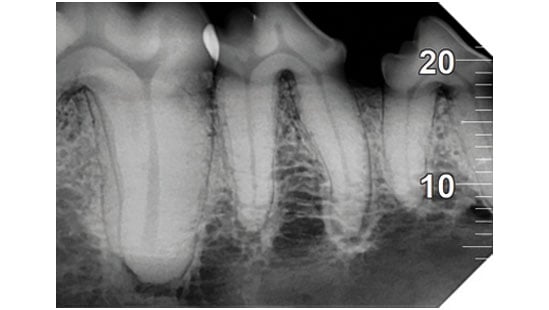

Analyse auf hohem Niveau

Das mit der zugehörigen Software integrierte System bietet hochmoderne Analysewerkzeuge und eine Auswahl spezifischer Filter, um die Lesbarkeit der Bilder gemäß den klinischen Anforderungen zu verbessern: